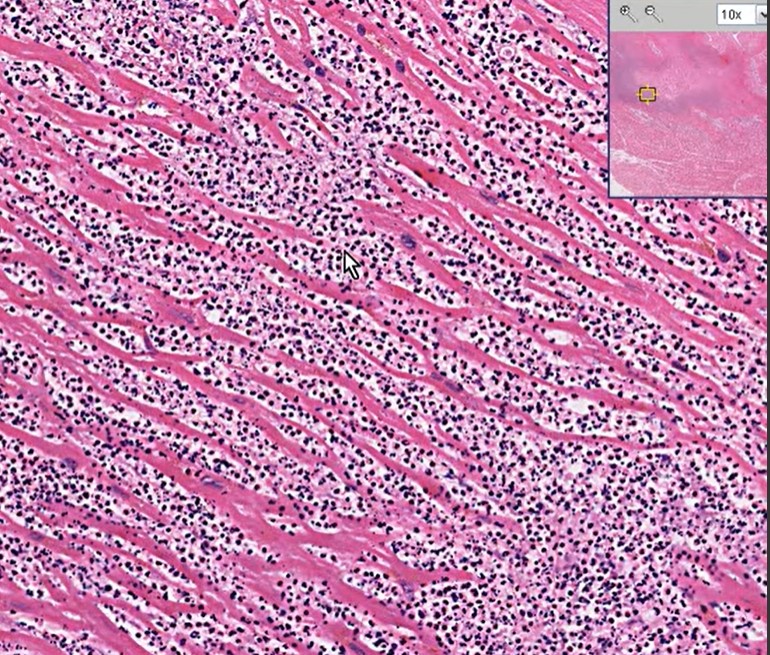

Ever since Wiggers introduced the overwhelming concept of LV systole and diastole, most of us ignored the fact that atria do have a separate contraction relaxation cycle, independent of what happens in the ventricle. Of course, atria and ventricles act as a single chamber in diastole. In reality, atria lack true boundaries when it acts as a conduit. The LA dimension varies considerably during the atrial cardiac cycle. Look at the LA pressure-volume loop, which can frighten anyone, with its horizontally lying figure of 8 pattern. During every cardiac cycle, the volume reaches atleast two troughs and one peak.

Don’t get frightened with this graph, spend some time, and you will get it right, Begin at “3” o clock position with the onset of diastole with a downsloping green loop, that continues as the red line of atrial contraction to end up in systole. The entire black loop, that happens during ventricular systole depicts the true reservoir function. with MV closed. ,